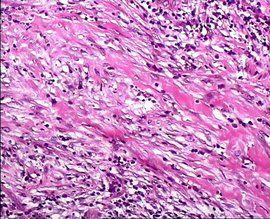

5.細針穿刺細胞學檢查(Fine-needleAspiration biopsy) 對結節處理很有幫助,該方法的廣泛套用大大減少了不必要的甲狀腺手術,提高了術中惡性腫瘤的發現率,減少了甲狀腺結節的處理費用。細針穿刺細胞學檢查的準確率達70%一90%,與穿刺及細胞學診斷的經驗有關。

(4)、 甲狀腺細針穿刺細胞學檢查

該檢查操作簡單、安全,對鑑別良惡性結節幫助很大。